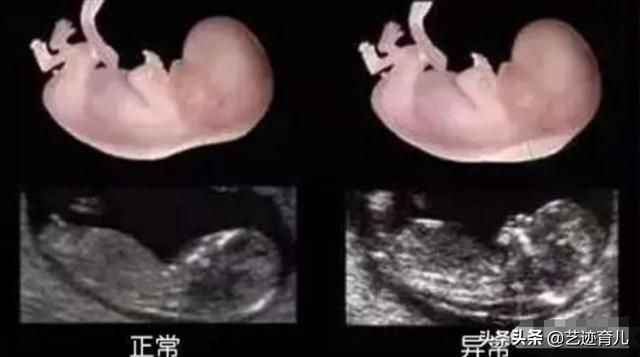

孕妈怀孕12周,开始第1个检查也是建档的时候,这个检查就是早唐,也叫NT检查,这个检查项目是检查唐氏综合症的第一步,主要是通过胎儿颈部透明带的厚度,来推断胎儿患有唐氏综合症的概率,这个时间一定不要超过13周,因为超过这个时间,胎儿颈部透明带就消失不见了。

NT值是排查的一个标准,如果NT检查结果的数值是小于等于3mm的话是属于正常的范围的,但是如果不合格的话,那么接下来的唐氏筛查也会借助,所以很多的孕妈唐氏筛查结果是低危,但是医生还会联系孕妈做一个无创DNA,很大因素是因为胎儿NT不合格,所以才交孕妈做无创DNA,有些地方无创DNA是免费的,但是如果收钱的话,1000-2500都有。

12周做的唐筛检查是早期唐筛检查,有血液学检查和超声检查。血液学检查是利用B-hcg 和血浆蛋白A的检查。超声部分是测量胎儿NT值(胎儿颈部透明层厚度)进行检查。联合两个检查结果,结合孕妇的年龄及其它情况,来推断胎儿患病风险,其准确率在85~90%左右。有的地区针对年轻没有不良孕产史和其它不良因素的孕妇就只推荐做早期唐筛。检查费用也比较便宜。